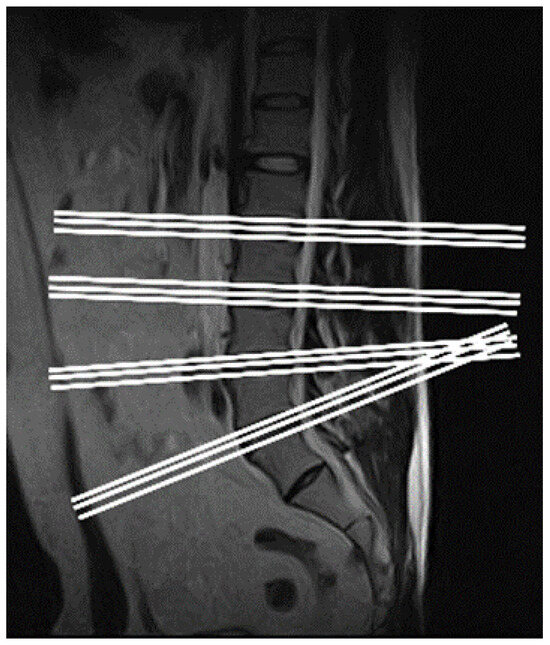

Figure 5 is the curve-fitting diagram of the spine. The rectangular frame is intercepted according to the normal and tangent of the spine fitting curve at the key points to ensure that the mask can completely cover the disc and the vertebra and that the direction is level with the mask.

Figure 5. Spine curve fitting and section cutting. (Left) A smooth spine curve was obtained by fitting the spine curve using the quadratic spline difference method. (Right) A rectangular slice of size (50/521*W, 150/521*H) is cut along the tangent direction of the fitted curve.